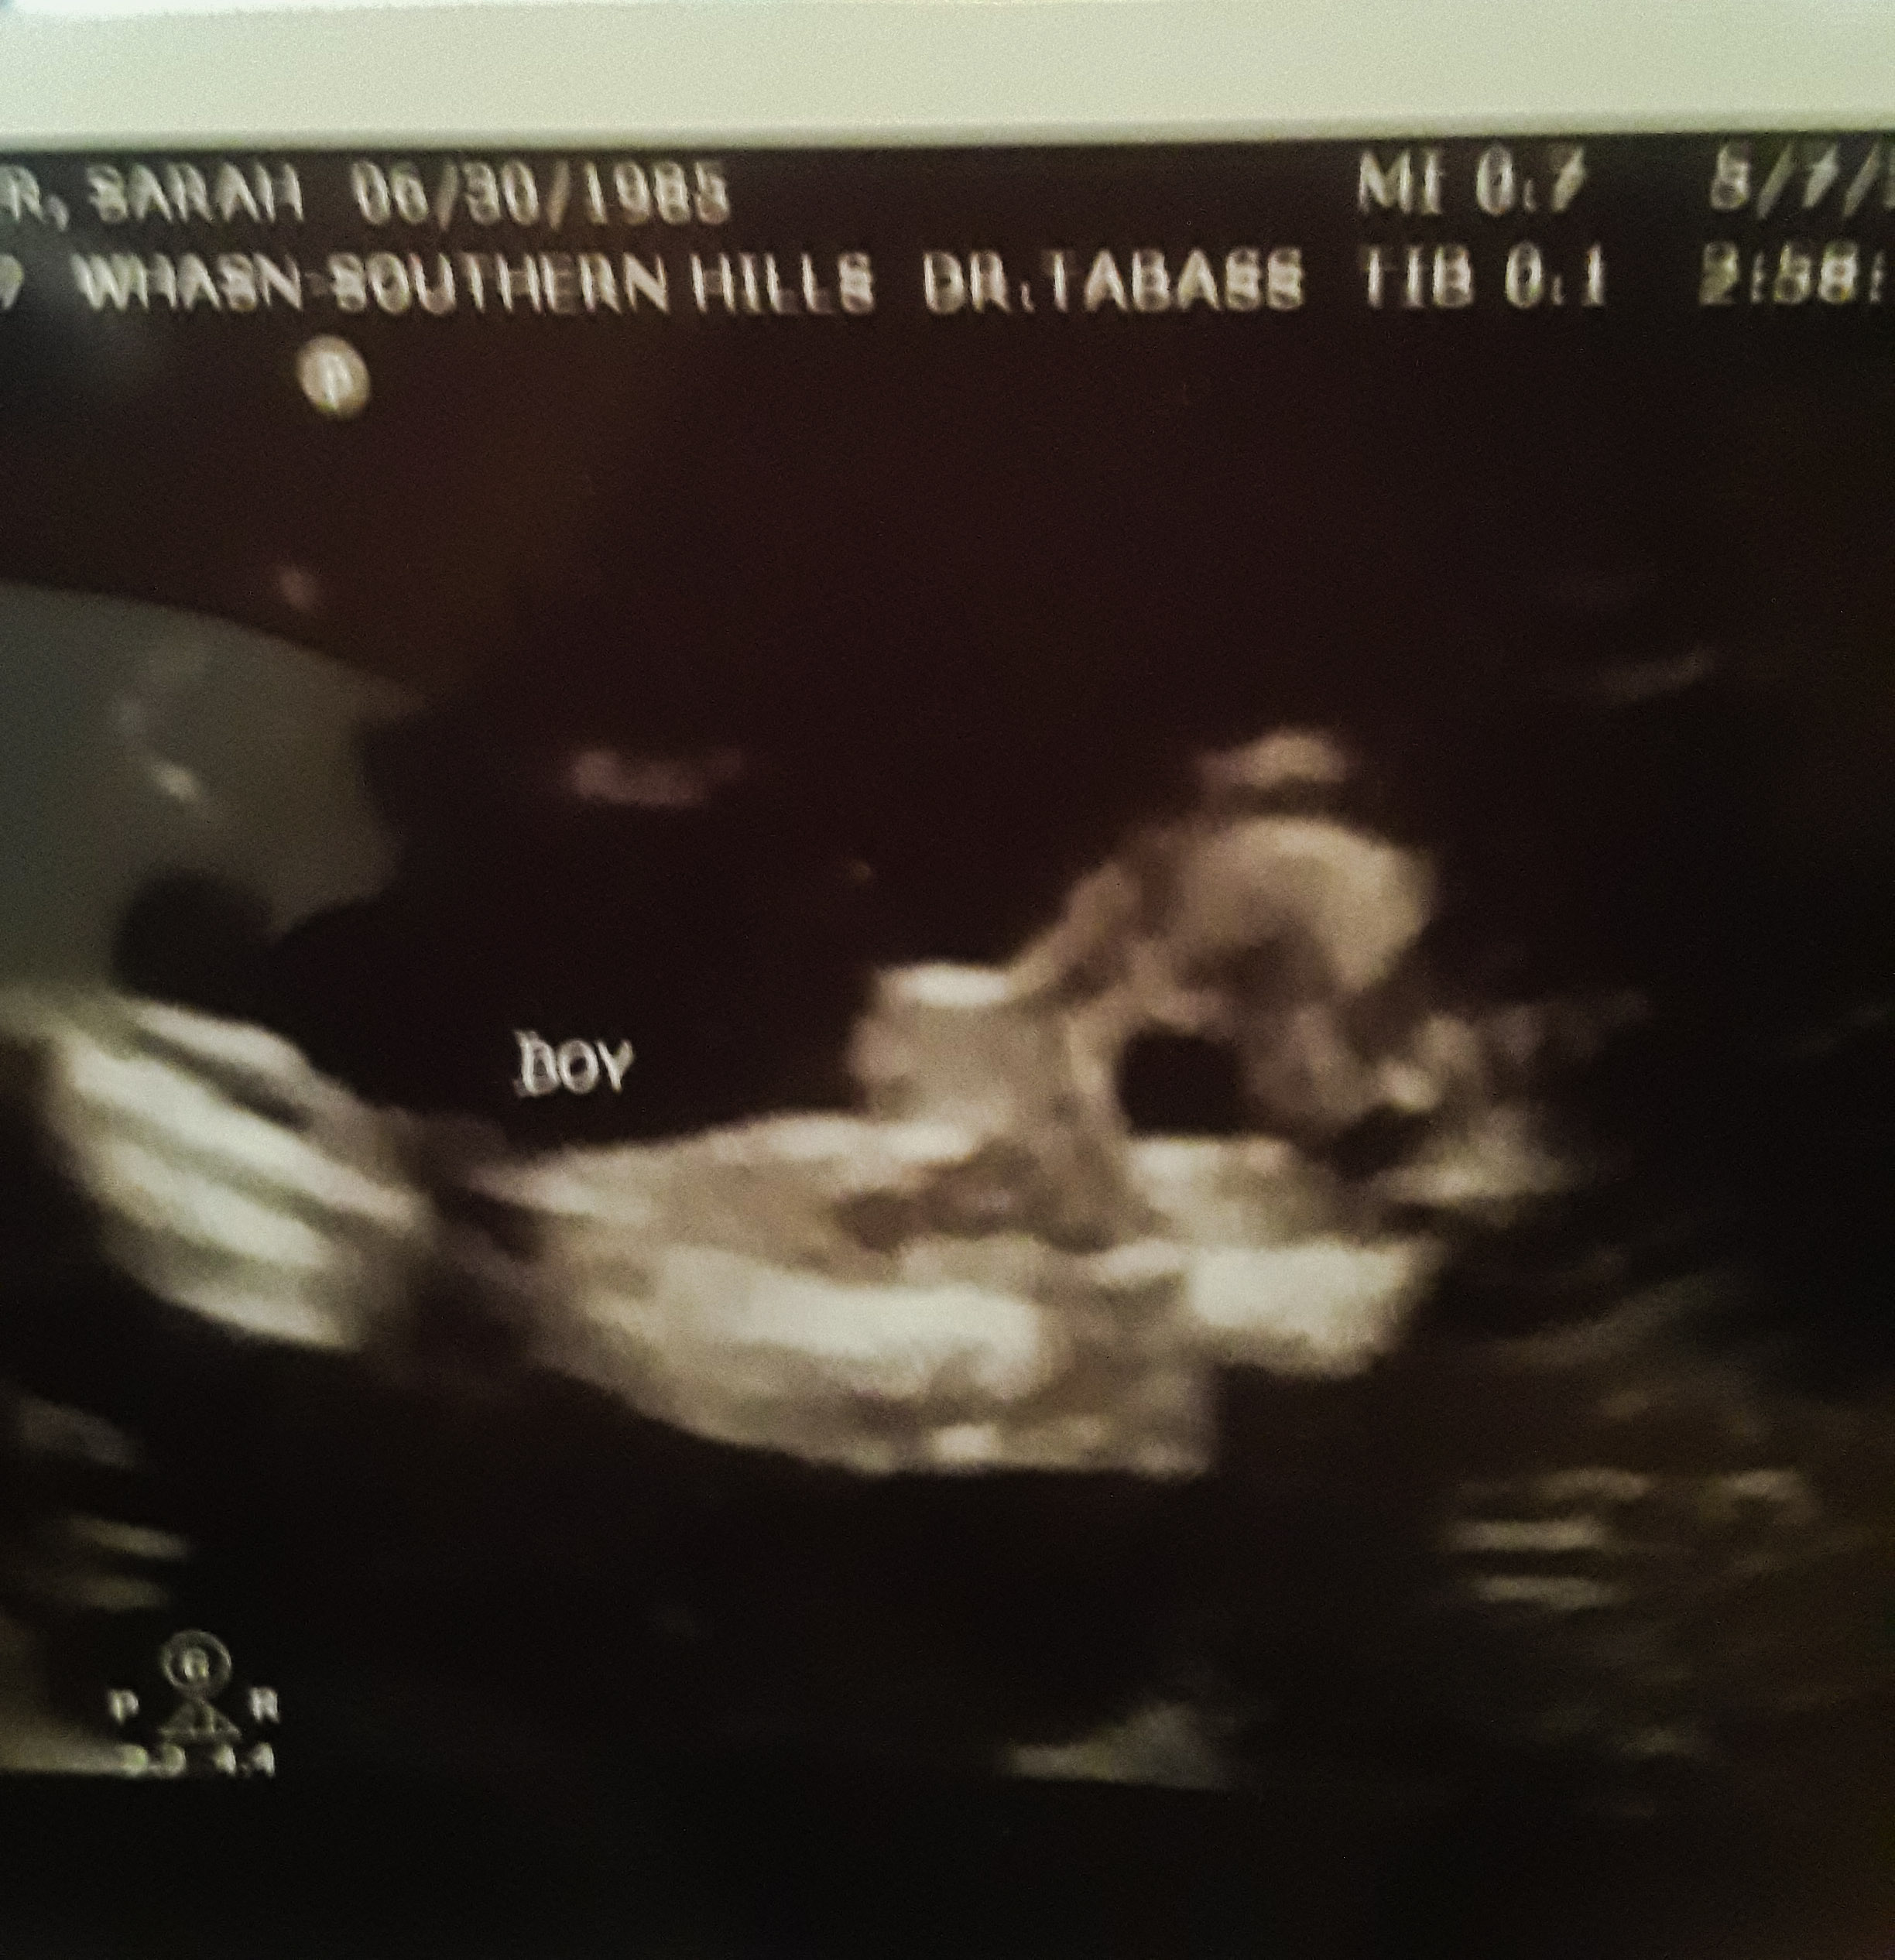

So my last ultrasound (roughly 17 weeks) was done by an ultrasound tech that seemed like she was really in a rush. She said boy, but I don't really feel like I have closure with that because I couldn't see a darn thing she was moving so fast. She gave me one scrambled egg looking printout that said boy with no arrows or circles or even telling me what body parts are in the shot. So I went back to my 12 week scan and I can't tell. Sometimes it looks like a girl and sometimes it looks like a boy. I am so confused. It might be petty to hope for a girl but between my son and stepkids I have raised 4 boys already! Help, what do you guys think?Attachment 41513Attachment 41512